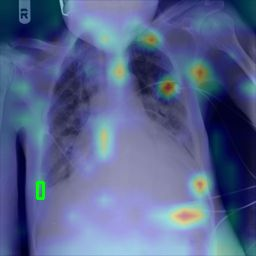

Deployments of artificial intelligence in medical diagnostics mandate not just accuracy and efficacy but also trust, emphasizing the need for explainability in machine decisions. The recent trend in automated medical image diagnostics leans towards the deployment of Transformer-based architectures, credited to their impressive capabilities. Since the self-attention feature of transformers contributes towards identifying crucial regions during the classification process, they enhance the trustability of the methods. However, the complex intricacies of these attention mechanisms may fall short of effectively pinpointing the regions of interest directly influencing AI decisions. Our research endeavors to innovate a unique attention block that underscores the correlation between 'regions' rather than 'pixels'. To address this challenge, we introduce an innovative system grounded in prototype learning, featuring an advanced self-attention mechanism that goes beyond conventional ad-hoc visual explanation techniques by offering comprehensible visual insights. A combined quantitative and qualitative methodological approach was used to demonstrate the effectiveness of the proposed method on the large-scale NIH chest X-ray dataset. Experimental results showed that our proposed method offers a promising direction for explainability, which can lead to the development of more trustable systems, which can facilitate easier and rapid adoption of such technology into routine clinics. The code is available at www.github.com/NUBagcilab/r2r_proto.